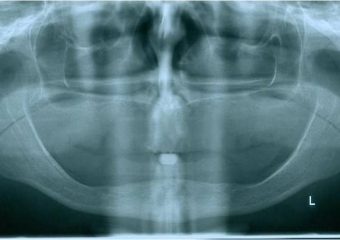

Raio x inicial - Clínica Cliniface

Raio x inicial